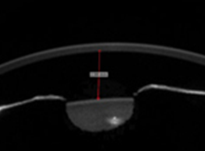

02안내렌즈삽입술 수술 전·후 검사

안내렌즈삽입술에는 각막의 전후면, 전방, 수정체 등 전안부에 대한 정확한 정보가 필요하며 수술 후에는 렌즈가 바른 위치에 고정되어 있는지 정기적으로 확인해야 합니다. Sirius는 렌즈가 삽입되는 전안부에 대한 정밀검사가 가능하므로 수술 전 부작용 예방 및 안전한 안내렌즈삽입술을 위한 필수 검사장비입니다.